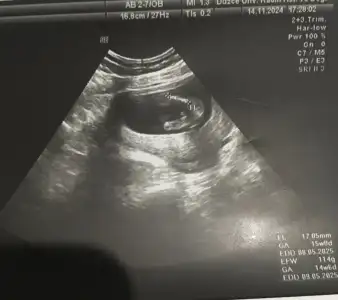

15. Hafta da erkek dendi 16 hafta da kız dendi ikisi de aynı doktor bakalım bir hafta sonra tekrar gidicem ne dicekler 🫣 15. Haftada ki ultrasonu da ekledim kesin konuşunca bizde ailelerimize erkek olduğunu küçük hediye ile söylemiştik bakalım nasip ne olucak 😂